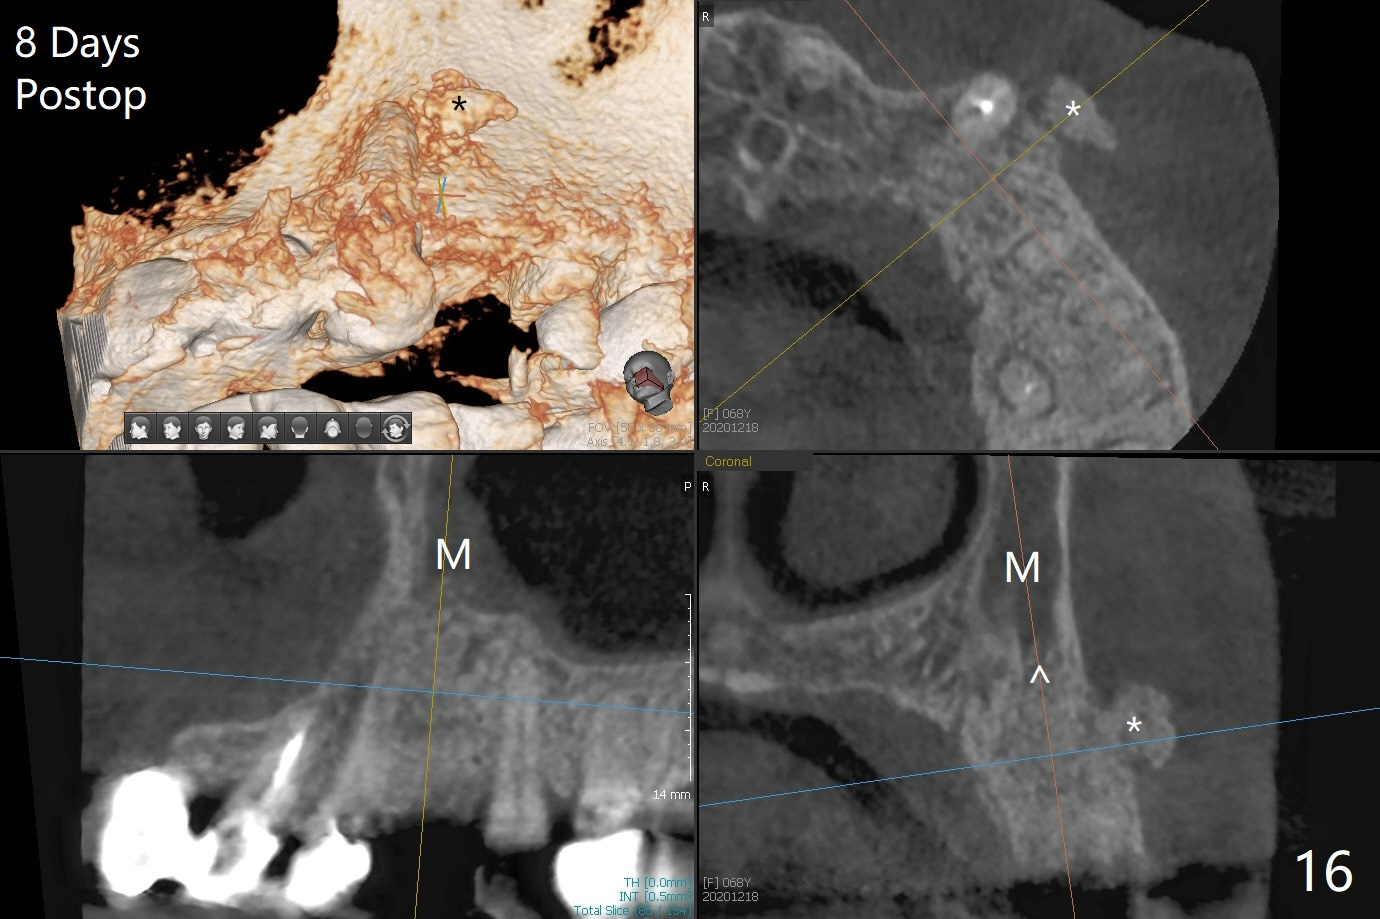

68岁女左上4颊侧瘘道(图一:*),与根尖颊侧骨板缺失相通,其实腭侧根尖周围病变更大(也与颊侧窝相通),术中没有注意腭侧根接近3(图二:P),稀里糊涂的基本顺着腭侧根(颊侧)走向钻洞(图四,与图三理想方向对比),突然记起术前设计钻洞必须在腭侧牙槽窝远中颊侧,在远中建立新洞眼(图五),之后无法再次建立新洞眼,只好利用同一个侧面切割钻头将钻洞往远中移位,同样效果不佳(图六),最后只好放弃,放置粘性骨粉(图七:*),覆盖PRF膜,6个月胶原膜,PGA缝线,牙周胶水。术后重新分析表明顺着腭侧牙槽窝种植与尖牙还是有分离(图八,九:*),因为牙槽窝是斜型的(图十:黑色),不过离颊侧骨板也接近(图八:B)。所以钻洞必须斜型针对远中骨壁,表浅些(图十一:红色箭头);一旦进入骨板,改变角度(图十二:红色箭头),适当矫枉过正,随着植体增大,钻洞会往近中偏移(白色箭头)。最好植体方向理想(图十三)。不过植骨后钻洞偏移可能性比较少。缝线和牙周胶水似乎是一个稳妥固定胶原膜方法。术后病人抱怨水肿严重,术后八天颊侧根尖隆起是由于骨粉推出骨板之外(图十五,十六:*),上颌窦底板无意穿孔(^)伴有上颌窦膜(M)增厚,与术前对比(图十七:上颌窦窦腔清晰)。术后一个月6个月吸收膜不见了,大多数缝线已经脱落,最后两根缝线撤除后,牙槽窝开口已经关闭,好像主要成分是骨粉(图十八)。术后5个月牙槽嵴宽,角化龈也宽,好像可以植入4x11.5毫米植体(图十九)。